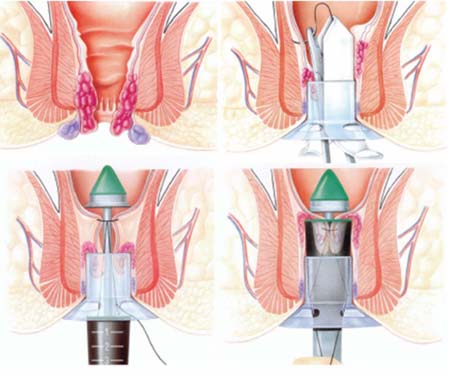

Hậu môn bị chít hẹp sau mổ: Dấu hiệu, phương pháp điều trị tại Tuyên Quang

Hậu môn bị chít hẹp sau mổ: Nguyên nhân và cách xử lý hiệu quả Hậu môn bị chít hẹp sau mổ là một biến chứng hậu phẫu…